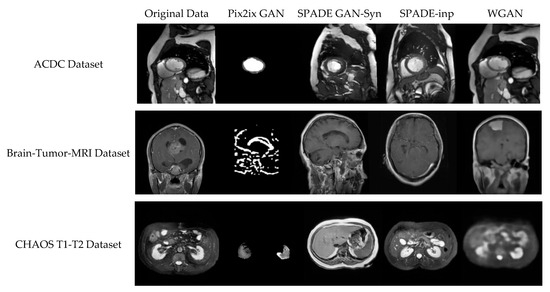

The rapid development of Generative Adversarial Networks (GANs) has transformed medical image processing, enabling realistic image synthesis, augmentation, and restoration. This study presents a comparative evaluation of three representative GAN architectures, Pix2Pix, SPADE GAN, and Wasserstein GAN (WGAN), across multiple medical imaging tasks,

The rapid development of Generative Adversarial Networks (GANs) has transformed medical image processing, enabling realistic image synthesis, augmentation, and restoration. This study presents a comparative evaluation of three representative GAN architectures, Pix2Pix, SPADE GAN, and Wasserstein GAN (WGAN), across multiple medical imaging tasks, including segmentation, image synthesis, and enhancement. Experiments were conducted on three benchmark datasets: ACDC (cardiac MRI), Brain Tumor MRI, and CHAOS (abdominal MRI). Model performance was assessed using Fréchet Inception Distance (FID), Peak Signal-to-Noise Ratio (PSNR), Structural Similarity Index (SSIM), Dice coefficient, and segmentation accuracy. Results show that SPADE-inpainting achieved the best image fidelity (PSNR ≈ 36 dB, SSIM > 0.97, Dice ≈ 0.94, FID < 0.01), while Pix2Pix delivered the highest segmentation accuracy (Dice ≈ 0.90 on ACDC). WGAN provided stable enhancement and strong visual sharpness on smaller datasets such as Brain Tumor MRI. The findings confirm that no single GAN architecture universally excels across all tasks; performance depends on data complexity and task objectives. Overall, GANs demonstrate strong potential for medical image augmentation and synthesis, though their clinical utility remains dependent on anatomical fidelity and dataset diversity.